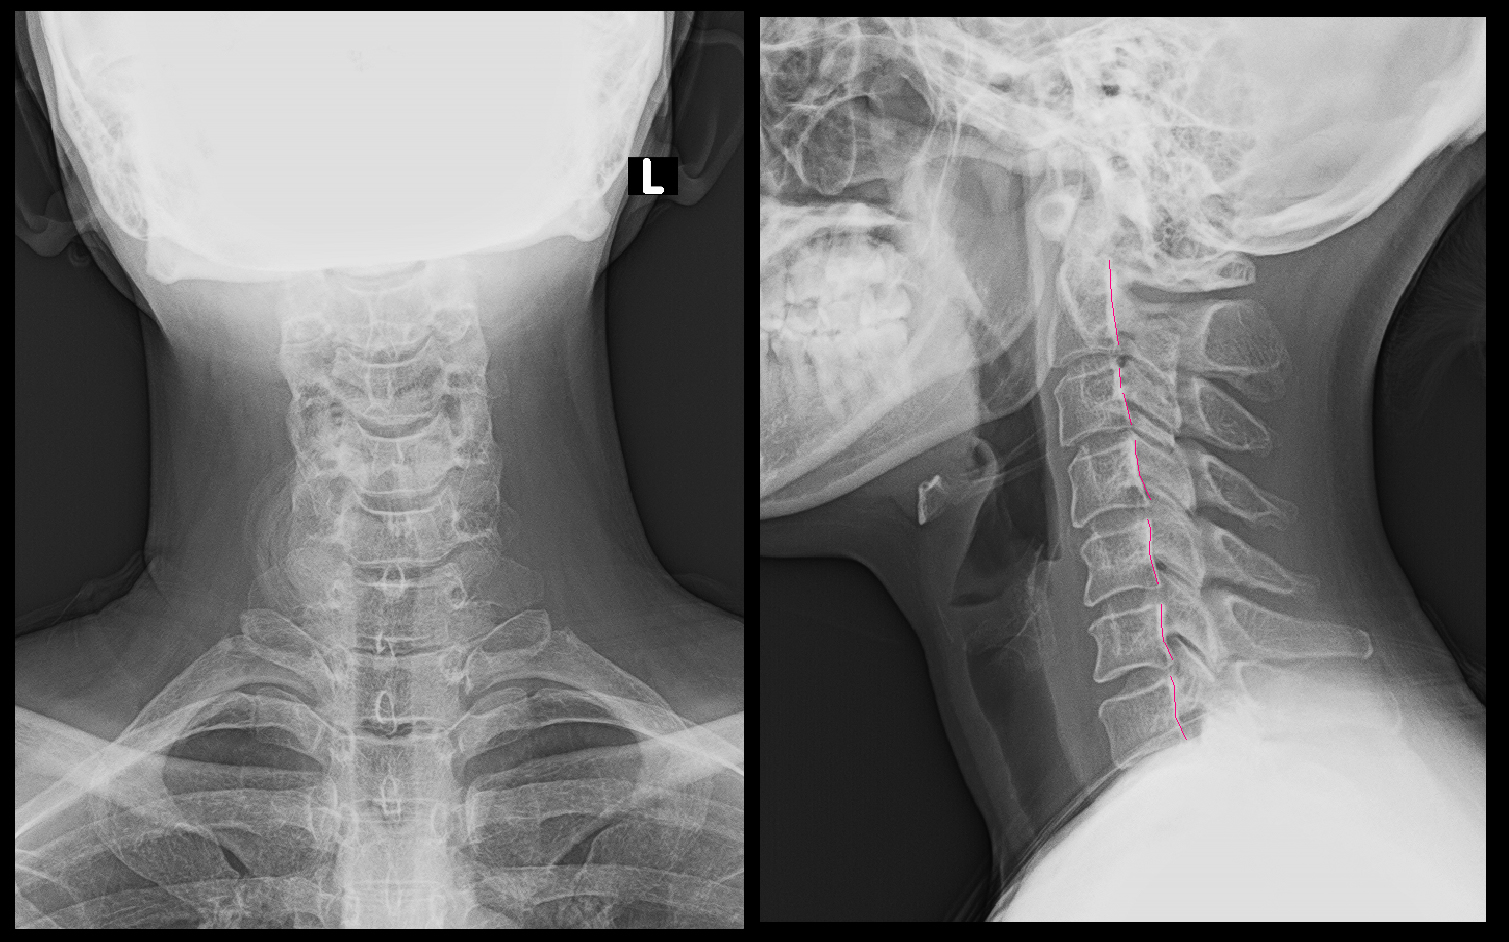

背中上部の症状は頚椎に起因することも多いので、頚椎のレントゲン像もチェックしています。

XpHW.jpg